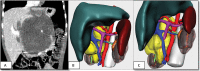

Introduction Three-dimensional (3D) technology is increasingly applied for planning challenging surgical interventions. We report our experience using 3D printing and virtual reconstruction for surgical planning of complex tumor resections in children. Methods Data were obtained from preoperative magnetic resonance. imaging analysis and 3D virtual recreations were performed using specialized computer software. 3D real-scale geometry models, including tumor, adjacent organs, and relevant vascularization, were printed in colorimetric scale and different materials for optimal structures discrimination. Results Four complex cases were selected. The first case was a bilateral Wilms tumor. The volumetric reconstruction proved the presence of enough healthy renal tissue, allowing bilateral nephron-sparing surgery. In the second case, reconstruction contributed to the location of pulmonary metastases. The third case was an abdominal neuroblastoma stage L2. The 3D model was of high value for planning and as a reference during the intervention. The last case is a cervico-thoracic neuroblastoma with an anatomopathological diagnosis of ganglioneuroma, located at the cervico-mediastinal juncture, in close relationship with the cervical vessels. Conclusions 3D reconstruction and the full-scale printing models are a useful tool in cases of complex tumor resections as they contribute to a better understanding of the relationships between the tumor and adjacent organs, helping to anticipate certain surgical complications. They also provide additional information to conventional imaging tests, being able to influence therapeutic decisions and facilitate the understanding by the family, improving doctor-patient communication.